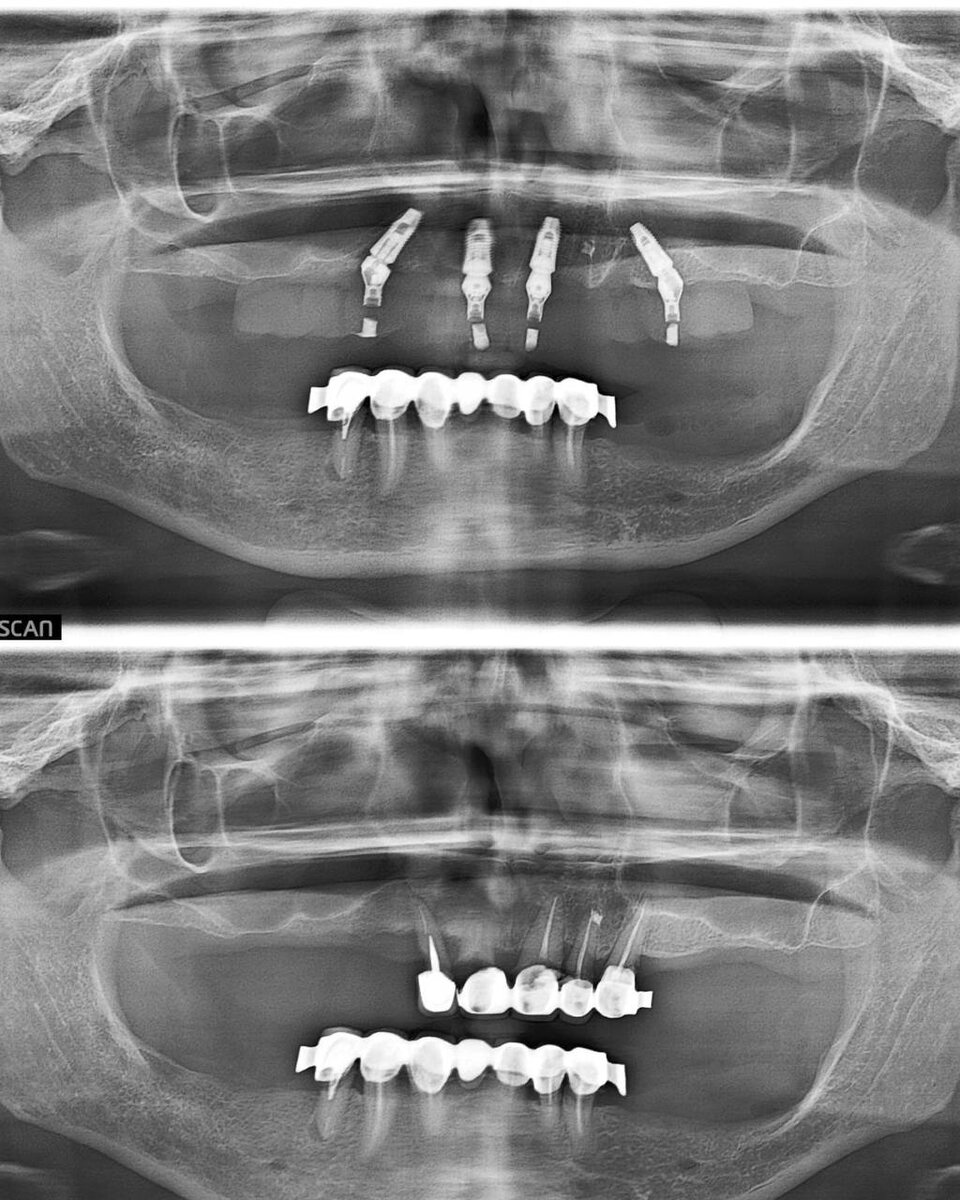

Тотальная реабилитация пациента.

Методика All on 4.

Как Вам результат?👇